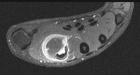

M.S. - 31 year old female complains of pain in her right first web space and index finger; pain began six months ago, but x-rays were not taken until recently since the patient was pregnant